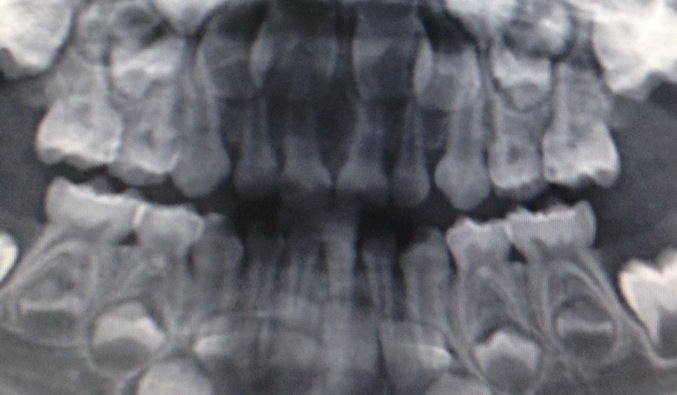

Вот увеличинла снимок:

Мне не нравится белая полоска у 61-62 зуба.....

Я бы сделала прицельный снимок левой стороны (61-62 зубы), мне тоже не нравится поперечная полоса, но, может быть, это артефакт?

На прицельном будет 100 процентов ясно!